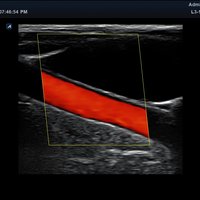

• Farbdoppler: farbige Darstellung der Richtung des Blutflusses